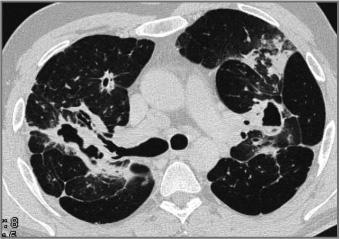

Der Radiologische Befund ist eine der klinischen Kriterien um die Tuberkulose zu diagnostizieren. Prof. Dr Gerhard Mostbeck betont gerade deshalb die Wichtigkeit, die gesamten radiologischen Möglichkeiten in der Diagnostik der Tuberkulose auszuschöpfen. Denn die Tuberkulose weist je nach Immunlage unterschiedlich Ausprägungsmöglichkeiten auf, kann alle Organsysteme befallen und simuliert viele andere Erkrankungen. In Abhängigkeit, ob es sich um eine Miliartuberkulose, Primärtuberkulose oder postprimäre Form handelt, können unterschiedliche charakteristische Veränderungen in der Bildgebung in Erscheinung treten. Das Lungenröntgen stellt den Grundpfeiler dar, auf dem sich die weiteren diagnostischen Methoden wie Sonographie, CT und MRT stützen und je nach Ausprägung und Organbefall eine exaktere Zuordnung zulassen. Professor Mostbecks Vortrag gibt einen praktischen Überblick über den richtigen und zielführenden Einsatz der bildgebenden Verfahren, um damit dem großen „Mimiker Tuberkulose“ auf die Schliche zu kommen.